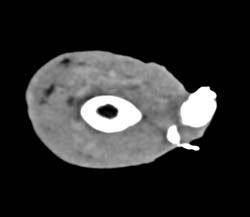

Diagnosis

Cellulitis Fluid